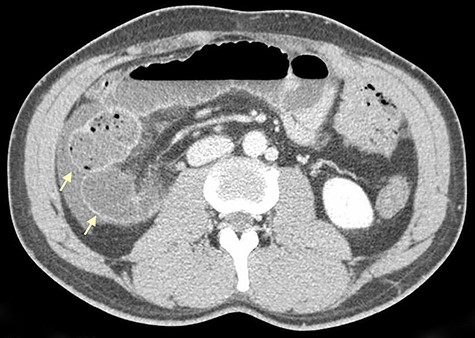

On physical examination, he was eupneic, hemodynamically stable and apyretic. His abdomen was soft, not distended, painless, with normal bowel sounds. Rectal examination showed an empty ampulla. Blood analysis revealed mild leukocytosis and little increase in C-reactive protein. Plain radiograph of the abdomen revealed dilated small bowel loops with air/fluid levels. Abdominal ultrasound revealed swollen intestinal loops on the right flank and interloop fluid. For further clarification, abdominal and pelvic computed tomography (CT) scan showed small bowel distension, air/fluid levels and free fluid (Fig. 1); signs of intestinal malrotation, with alteration of the normal topography of the duodenal arch (Fig. 2) and retrocecal position of terminal ileum (Fig. 3).

Sagittal CT scan shows small bowel distension with air/fluid levels (arrows).